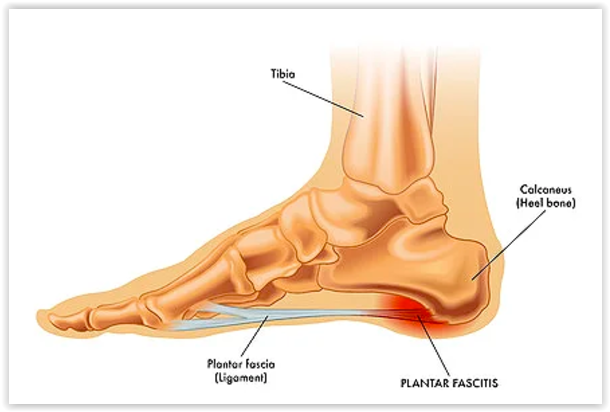

足底筋膜炎是足踝外科中常见的一种疾病,指的是足底筋膜发生炎症,导致足跟部或足底区域出现疼痛。足底筋膜是连接脚跟骨与脚趾的坚韧韧带组织,起到支撑脚弓、缓冲冲击的作用。由于过度使用、长时间站立、运动过量或脚部姿势不良等因素,足底筋膜长期承受过度拉伸或压力,从而导致微小的撕裂和炎症反应。这种疾病通常表现为早晨起床后的第一步痛感最为明显,疼痛常伴随活动后逐渐缓解,但长时间站立或剧烈运动后可能会加重。足底筋膜炎通常是一种慢性疾病,症状可能持续数月,甚至影响日常生活和工作。因此,及时诊断和治疗对于缓解症状、恢复足部功能至关重要。

超声检查是目前诊断足底筋膜炎的一项非常实用且经济的工具。通过超声波,医生可以实时观察足底筋膜的状态,评估其是否增厚、是否有炎症,或者是否存在微小的撕裂等病变。超声还可以用来检测足底筋膜的血流情况,进一步了解炎症的程度。超声检查操作性强,且成本相对较低,因此在临床上被广泛应用于足底筋膜炎的诊断。